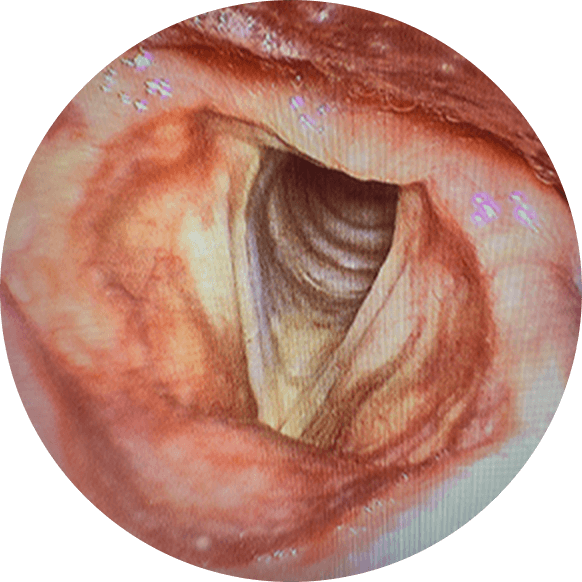

전문의의 내시경 검사